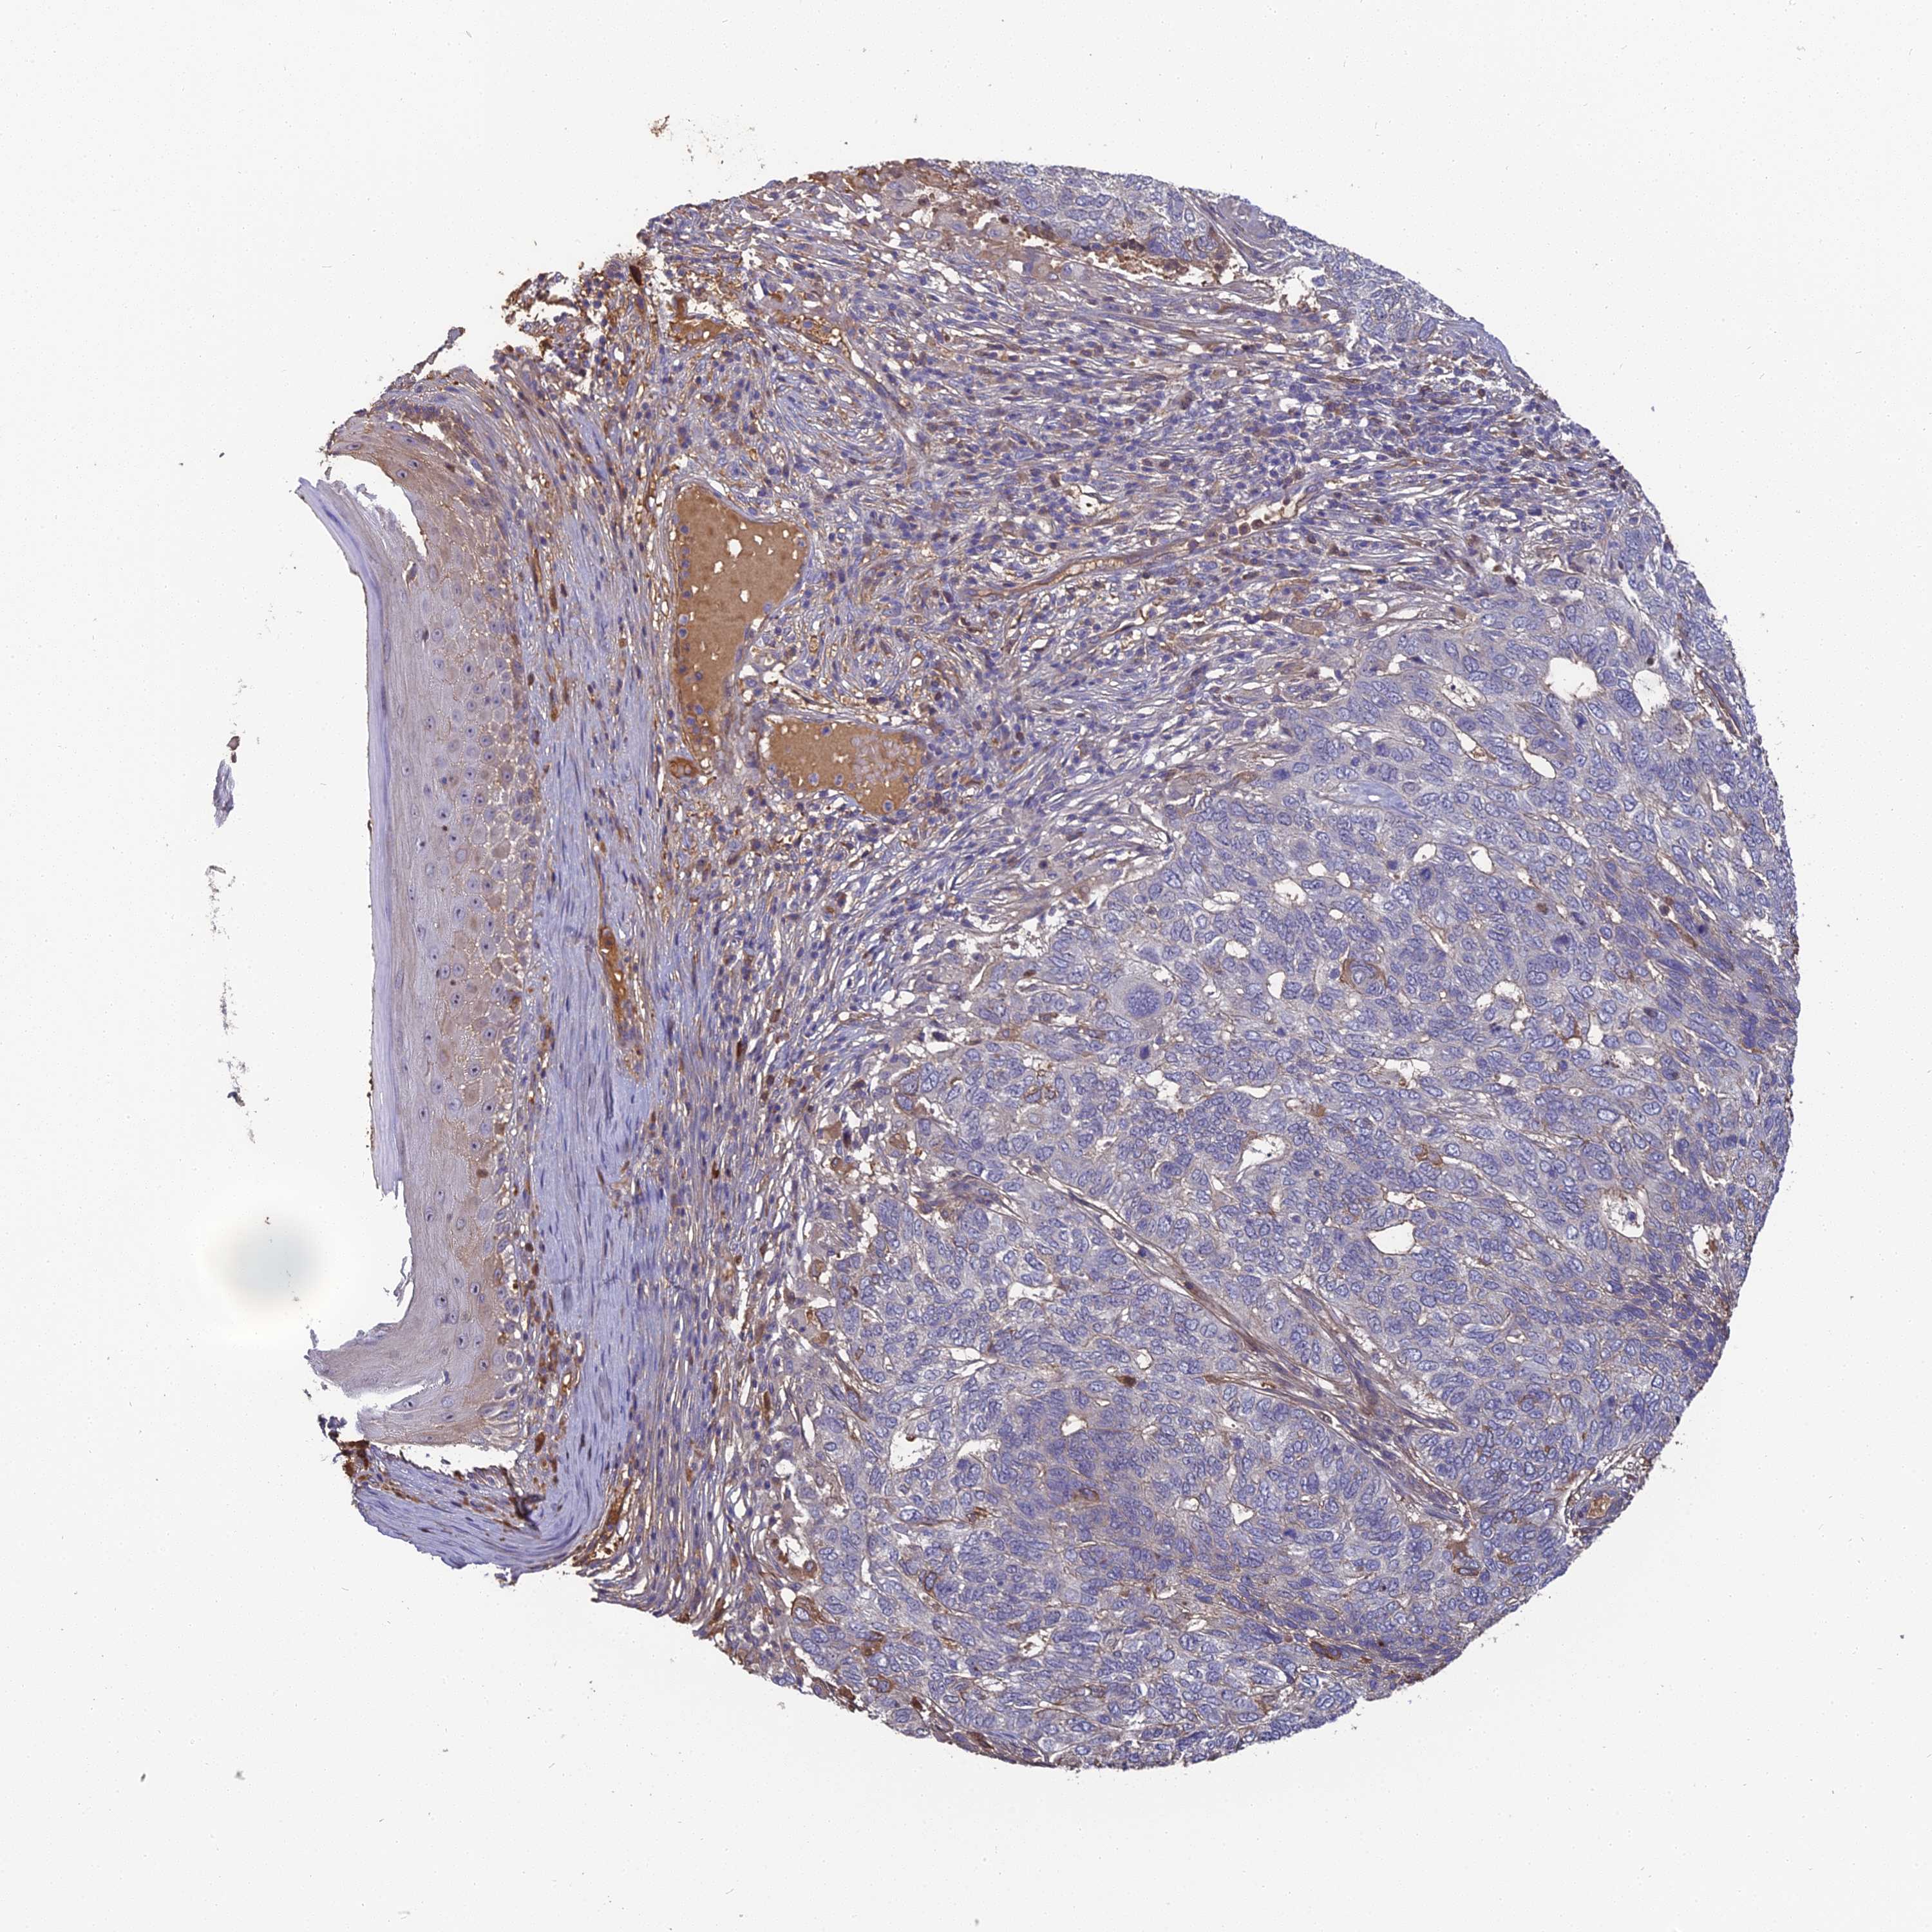

SKIN CANCER - Protein expressioni

A mouse-over function shows sample information and annotation data. Click on an image to view it in a full screen mode. Samples can be filtered based on level of antibody staining by selecting one or several of the following categories: high, medium, low and not detected. The assay and annotation is described here.

Antibody stainingi

Antibody staining in the annotated cell types in the current human tissue is reported as not detected, low, medium, or high, based on conventional immunohistochemistry profiling in selected tissues. This score is based on the combination of the staining intensity and fraction of stained cells.

Each image is clickable and will lead to virtual microscopy that enables deeper exploration of all samples and also displays staining intensity scores, fraction scores and subcellular localization as well as patient and tissue information for each sample.

Antibody HPA042573

Staining

High

Medium

Low

Not detected

Intensity

Strong

Moderate

Weak

Negative

Quantity

>75%

75%-25%

<25%

None

Location

Nuclear

Cytoplasmic/membranous

Cytoplasmic/membranous,nuclear

Basal cell carcinoma

Squamous cell carcinoma, NOS

Squamous cell carcinoma, metastatic, NOS